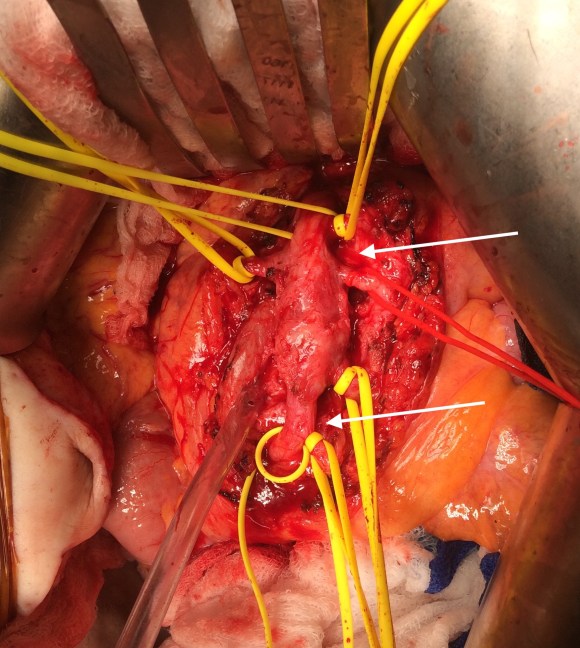

The Penumbra was effective in removing much of the fresh thrombus, but I was also cognizant of the fact that pulling out the catheter will draw clot into the 8F sheath that did not make it into the catheter. I placed a wire, and removed the sheath to expel much of the bulky thrombus (picture below).

The completion angiogram (below) doesn’t show the intermediate angiograms showing thrombus that embolized to other arteries as I manipulated the catheters and thrombectomized -I was able to successfully retrieve these with selective catheterization, another neurointerventional series of maneuvers that I have successfully borrowed.

After being satisfied with the completion, I removed the sheaths and explored the abdomen finding this segment of infarcted small bowel (next image).